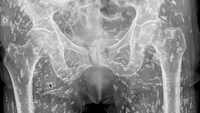

Seorang dokter UGD di Florida membagikan salah satu hasil rontgen paling mencengangkan yang pernah dilihatnya. Foto rontgen tersebut memperlihatkan tubuh bagian bawah seseorang dipenuhi ratusan telur cacing pita.  (Foto: Tangkapan Layar X).